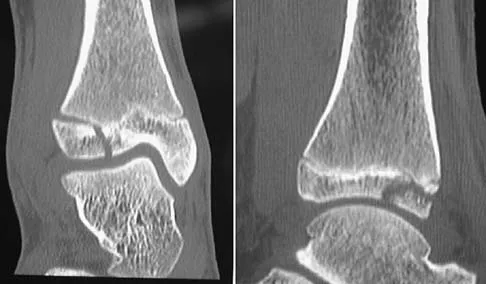

Figure 7 shows the CT scan of a 25-year-old soccer player who has had posterior ankle pain with plantar flexion for the past 2 years. Immobilization has failed to provide relief. He is ambulatory. Management should consist of

Explanation

An os trigonum is usually asymptomatic, but this accessory bone has been associated with persistent posterior ankle pain, which has been described as os trigonum syndrome. This usually affects athletes and ballerinas. Forced plantar flexion leads to impingement of the os trigonum against the posterior tibial plafond, and flexor hallucis tendinitis may develop. It may be difficult to differentiate a fractured trigonal process from the os trigonum. MRI may reveal bone marrow edema that may aid in the diagnosis of os trigonum syndrome. Steroid injections may lead to tendon rupture. The results of excision of a symptomatic os trigonum through a posteromedial or lateral approach are favorable, with a rapid return to full function. The main complication of this procedure is sural nerve injury with a lateral approach. Hedrick MR, McBryde AM: Posterior ankle impingement. Foot Ankle Int 1994;15:2-8.

- Abramowitz Y, Wollstein R, Barzilay Y, et al: Outcome of resection of a symptomatic os trigonum. J Bone Joint Surg Am 2003;85:1051-1057.